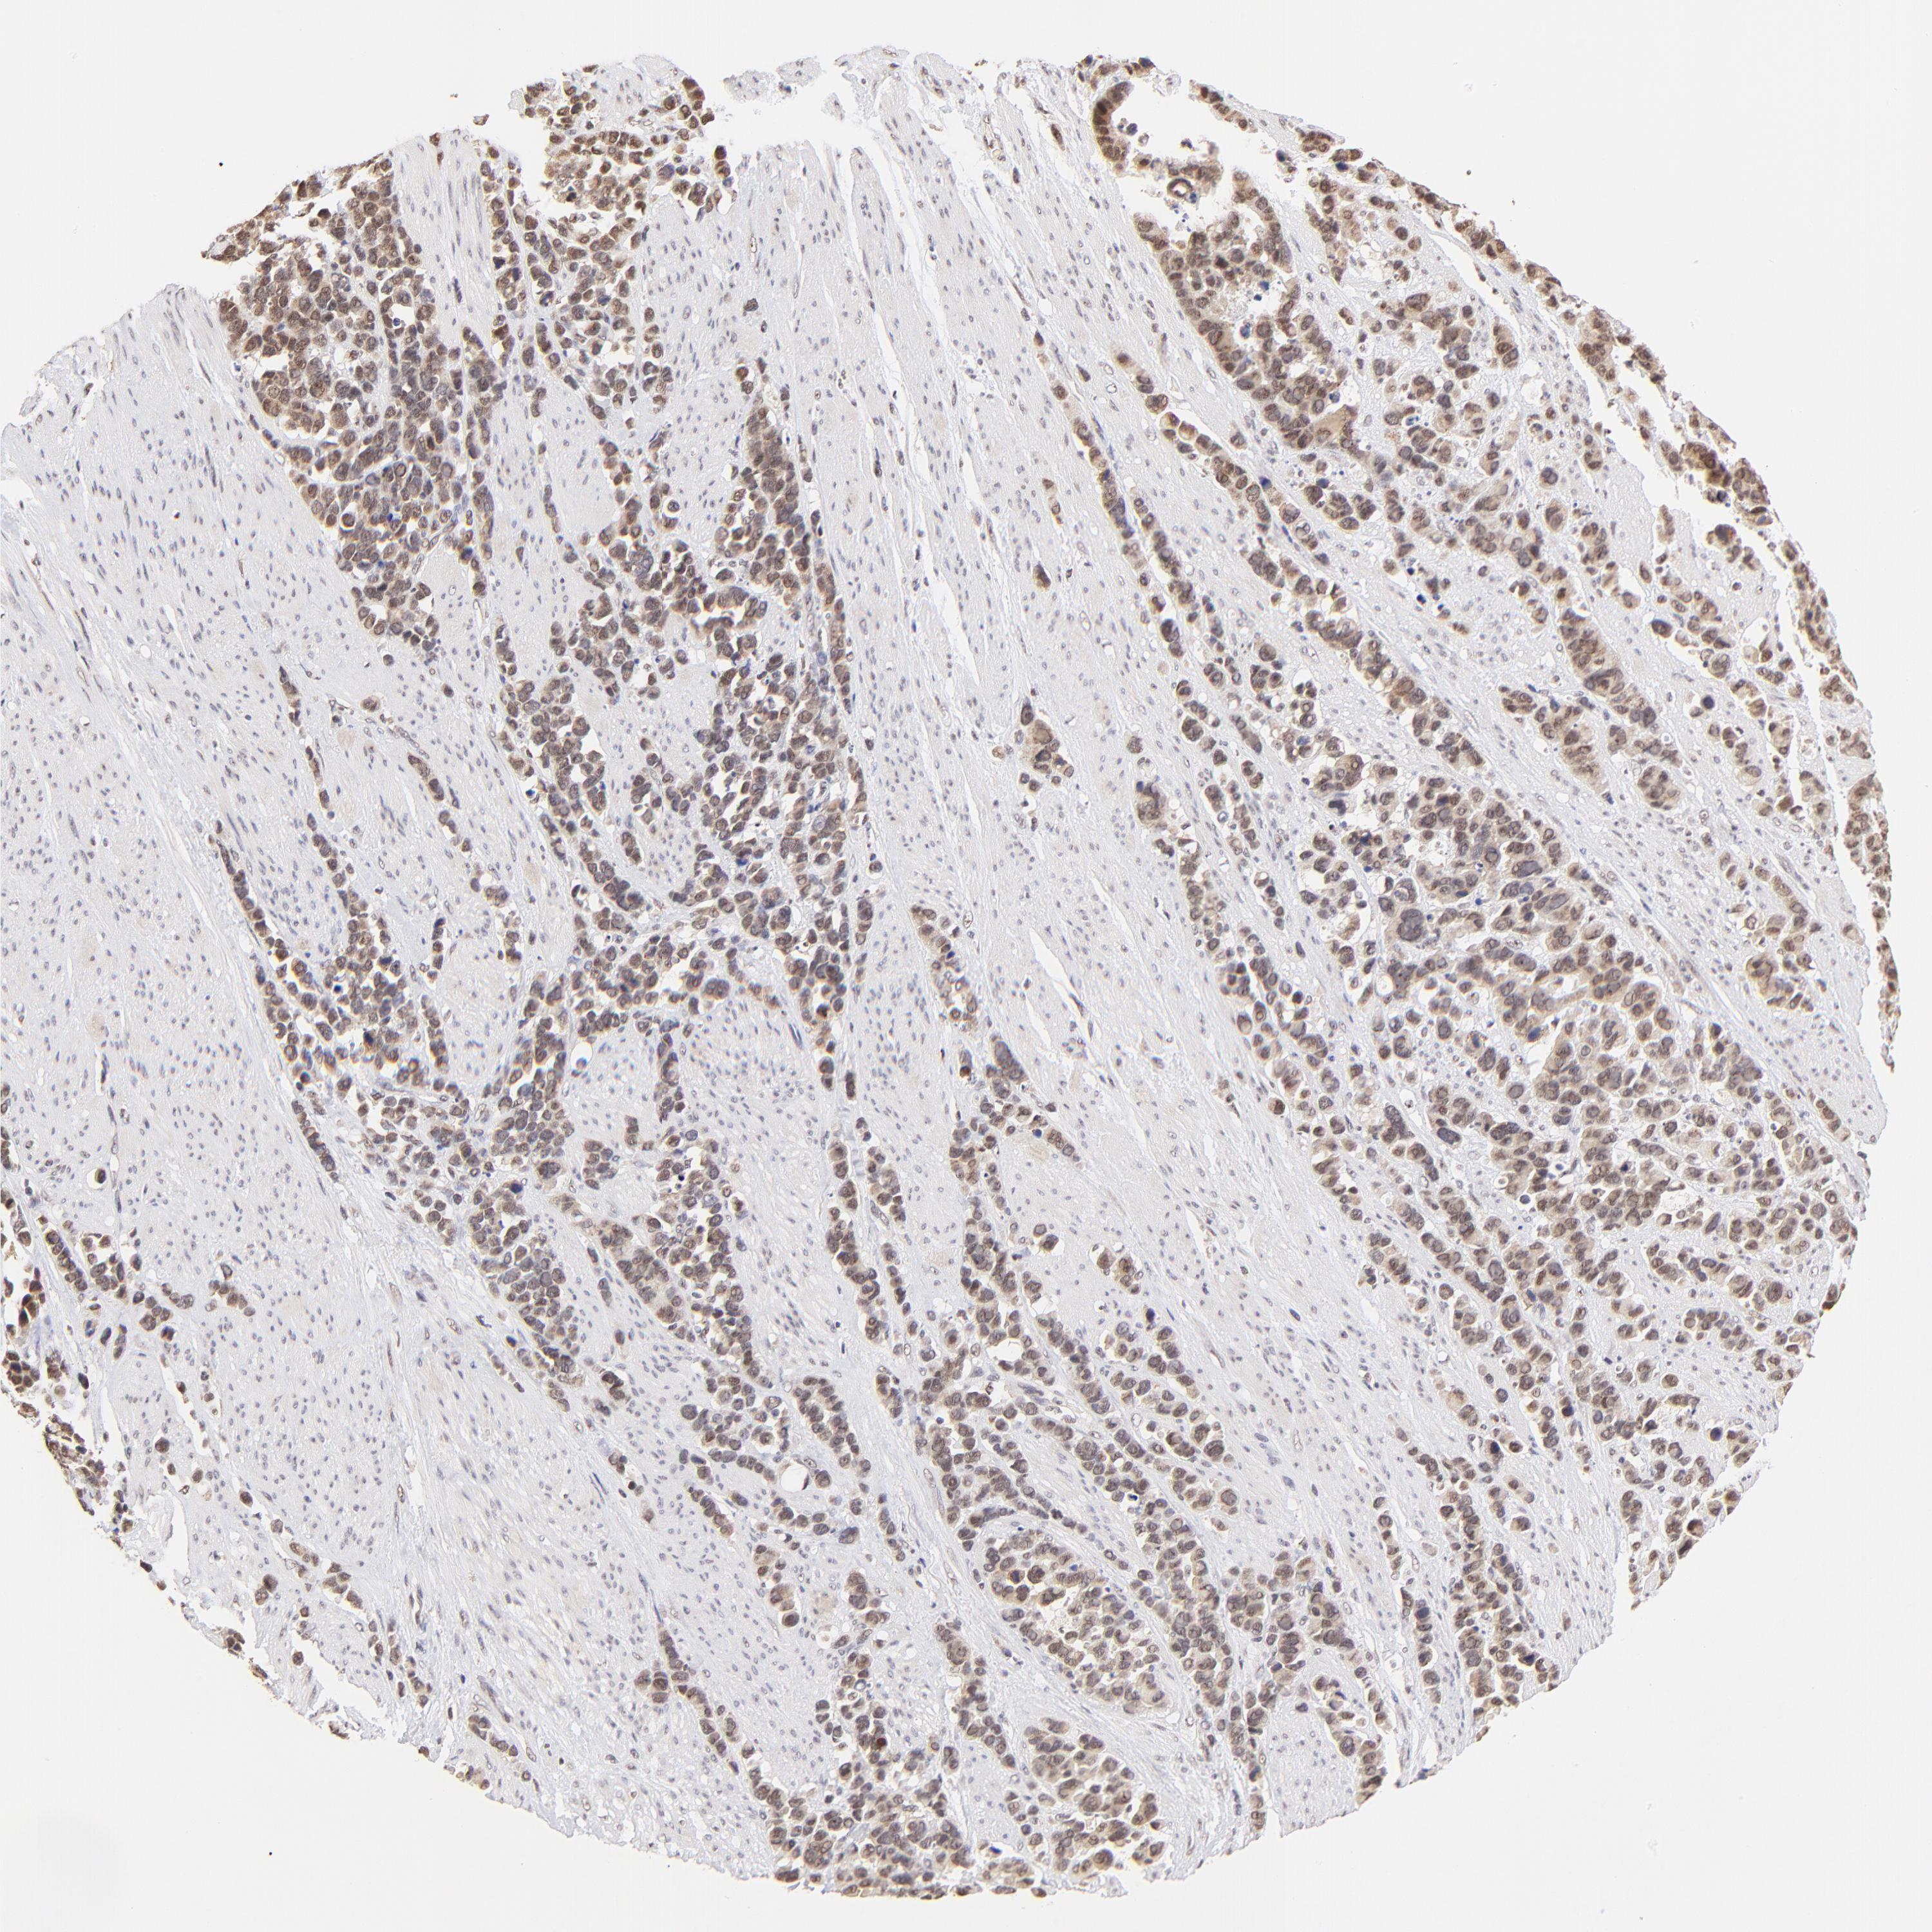

STOMACH CANCER - Protein expressioni

A mouse-over function shows sample information and annotation data. Click on an image to view it in a full screen mode. Samples can be filtered based on level of antibody staining by selecting one or several of the following categories: high, medium, low and not detected. The assay and annotation is described here.

Note that samples used for immunohistochemistry by the Human Protein Atlas do not correspond to samples in the TCGA dataset.

Antibody stainingi

Antibody staining in the annotated cell types in the current human tissue is reported as not detected, low, medium, or high, based on conventional immunohistochemistry profiling in selected tissues. This score is based on the combination of the staining intensity and fraction of stained cells.

Each image is clickable and will lead to virtual microscopy that enables deeper exploration of all samples and also displays staining intensity scores, fraction scores and subcellular localization as well as patient and tissue information for each sample.

Antibody HPA003142

Staining

High

Intensity

Strong

Quantity

>75%

Location

Nuclear

Adenocarcinoma, NOS